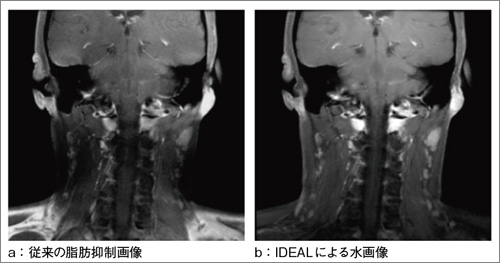

図5 IDEALの効果

従来の脂肪抑制画像(a)に比べて,IDEALによる水画像(b)では良好な脂肪抑制画像が得られている。

(画像ご提供:磐田市立総合病院様)